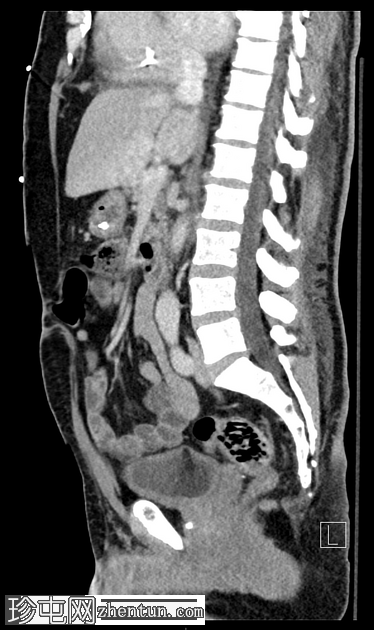

轴向C+门静脉期

小脐疝伴Richter疝,包含小肠前壁(肠系膜对侧部分),无梗阻或并发症。